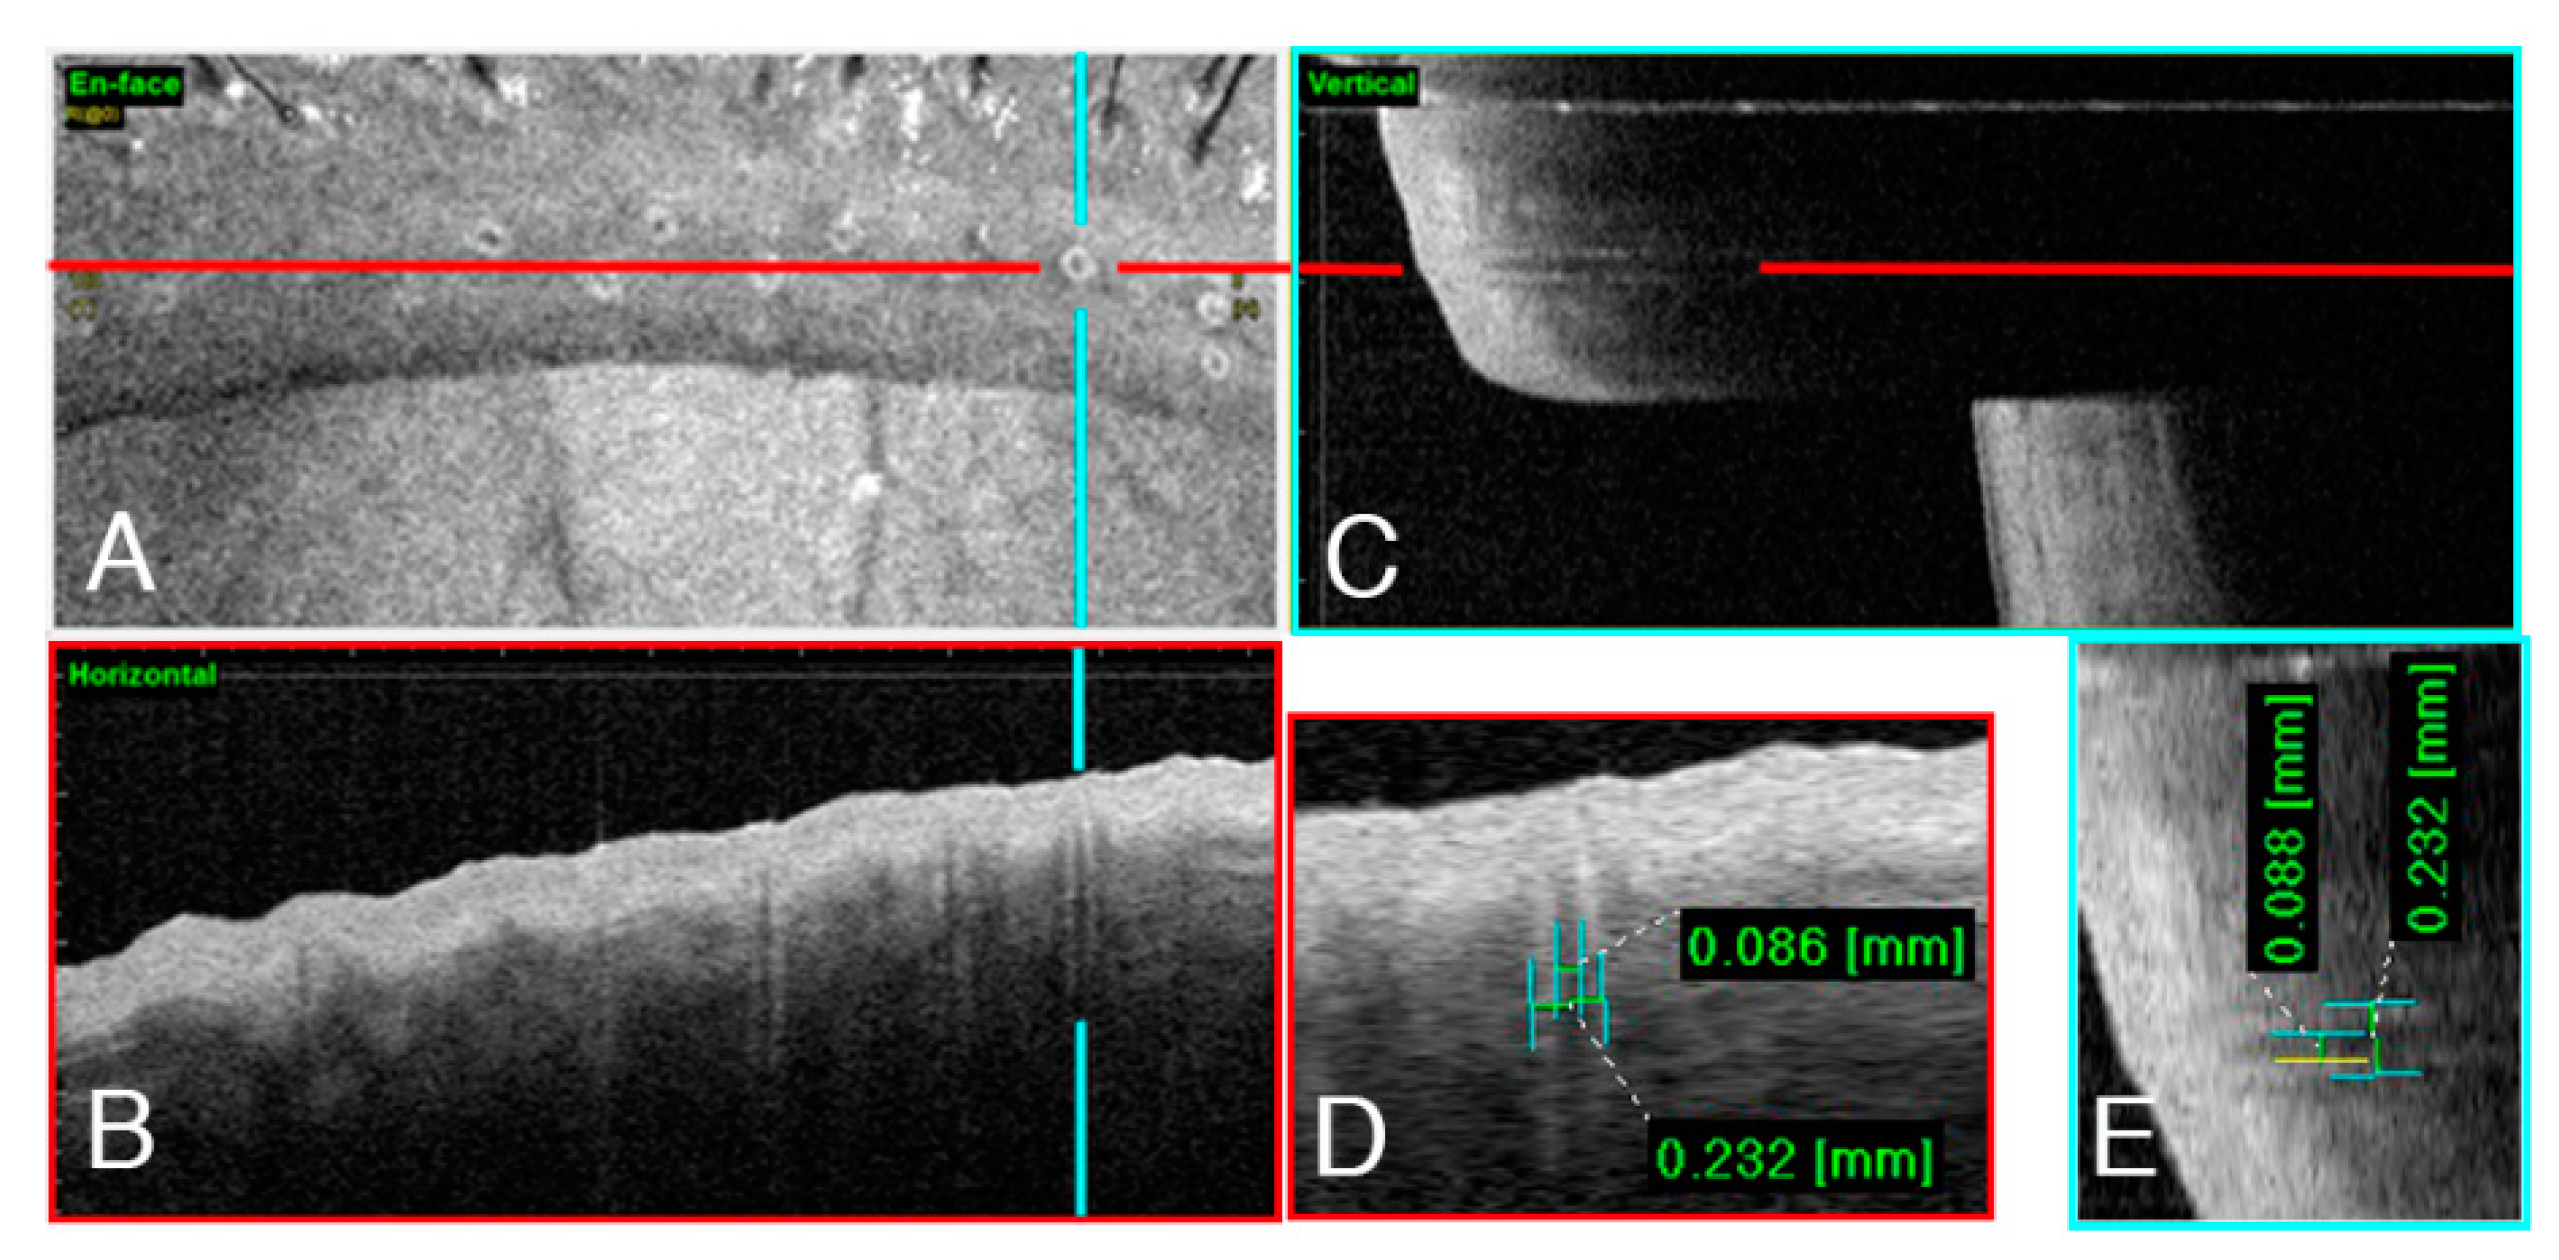

3.1. Morphology of the Meibomian Gland Openings